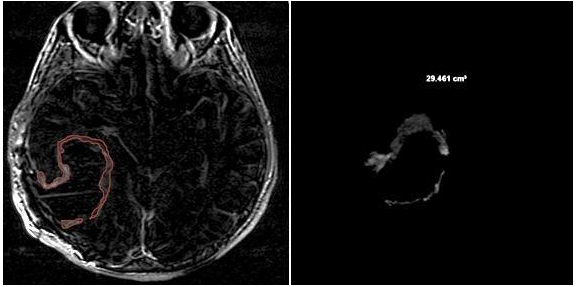

3.2. Quantitative Analysis